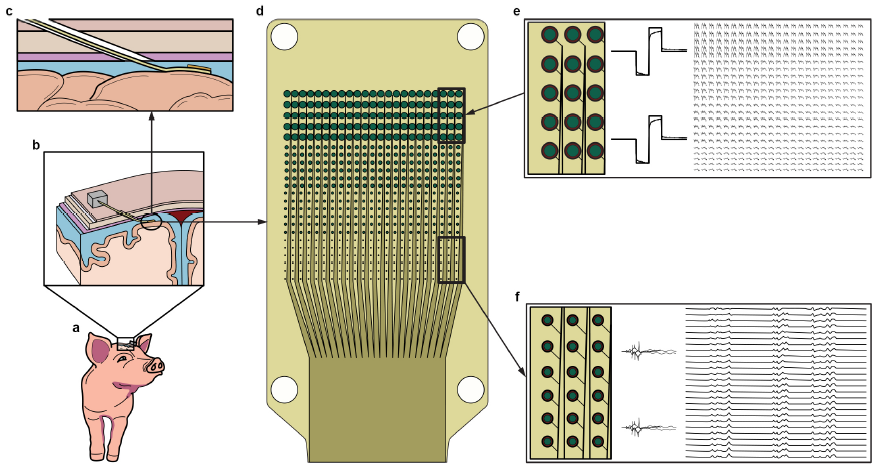

下图为系统概述。该系统配置用于体内神经记录和刺激,包括一组模块化薄膜微电极阵列,设计用于使用新型“cranial micro-slit”技术进行快速、微创硬膜下植入。每个微电极阵列包含 529个电极,直径范围从 20 到 200 μm,并连接到定制的硬件接口。硬膜下阵列植入后,每个微电极阵列模块的互连电缆穿过硬脑膜切口和颅骨微裂隙切口。整个系统配置如图1所示。

图1 系统概述